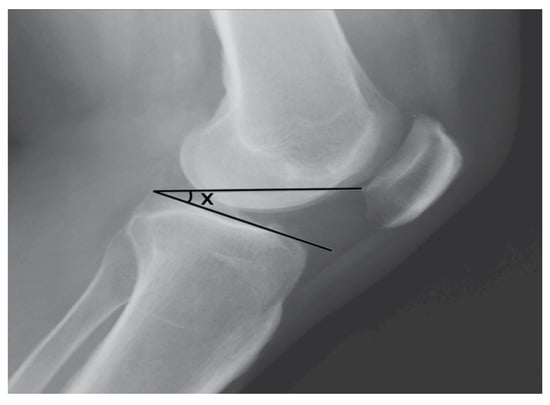

- Portner, O.; Pakzad, H. The evaluation of patellar height: A simple method. J. Bone Jt. Surg. Am. 2011, 93, 73–80. [Google Scholar] [CrossRef]